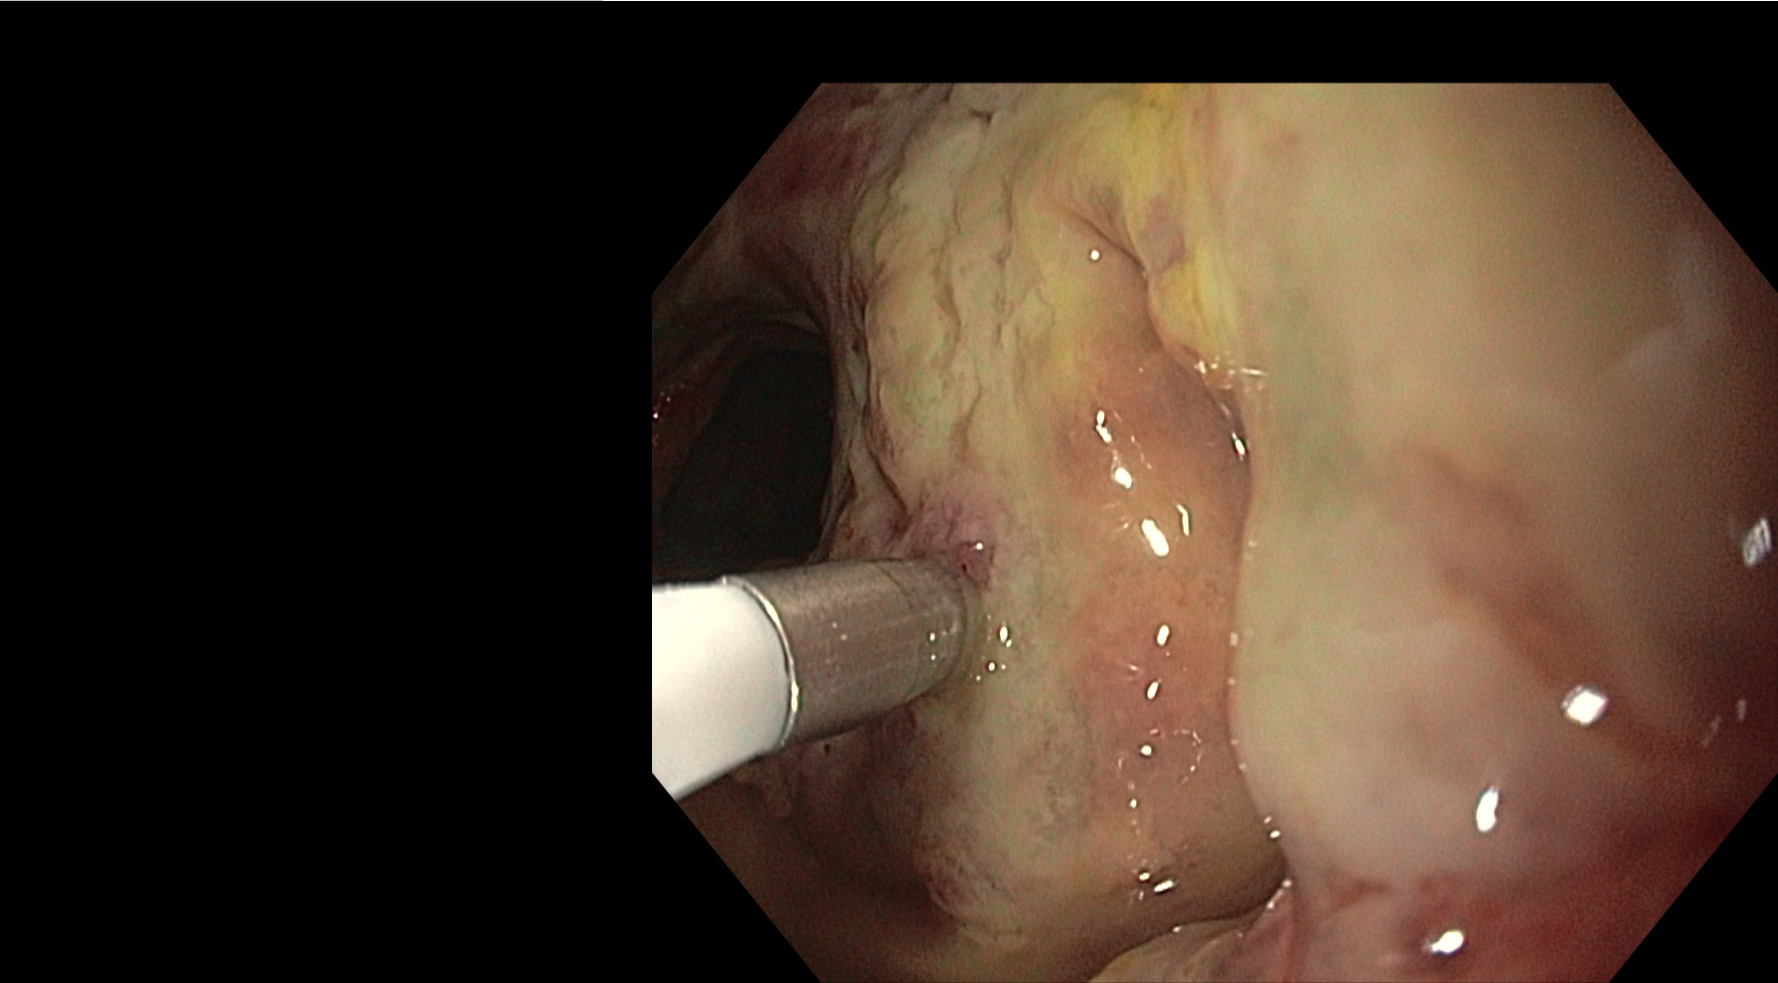

Start of first IBD study

The VISION study is the first study that focussed on IBD pathology. In this study Vedolizumab-800CW is utilized to identify inflamed gut mucosa using near-infrared fluorescence molecular endoscopy (NIR-FME), spectroscopy and confocal laser endomicroscopy (CLE).